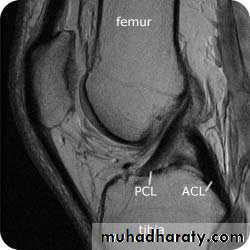

2.MRI

.Meniscal & ligamentous tears in the knee .

.Rotator cuff tears of the shoulder .